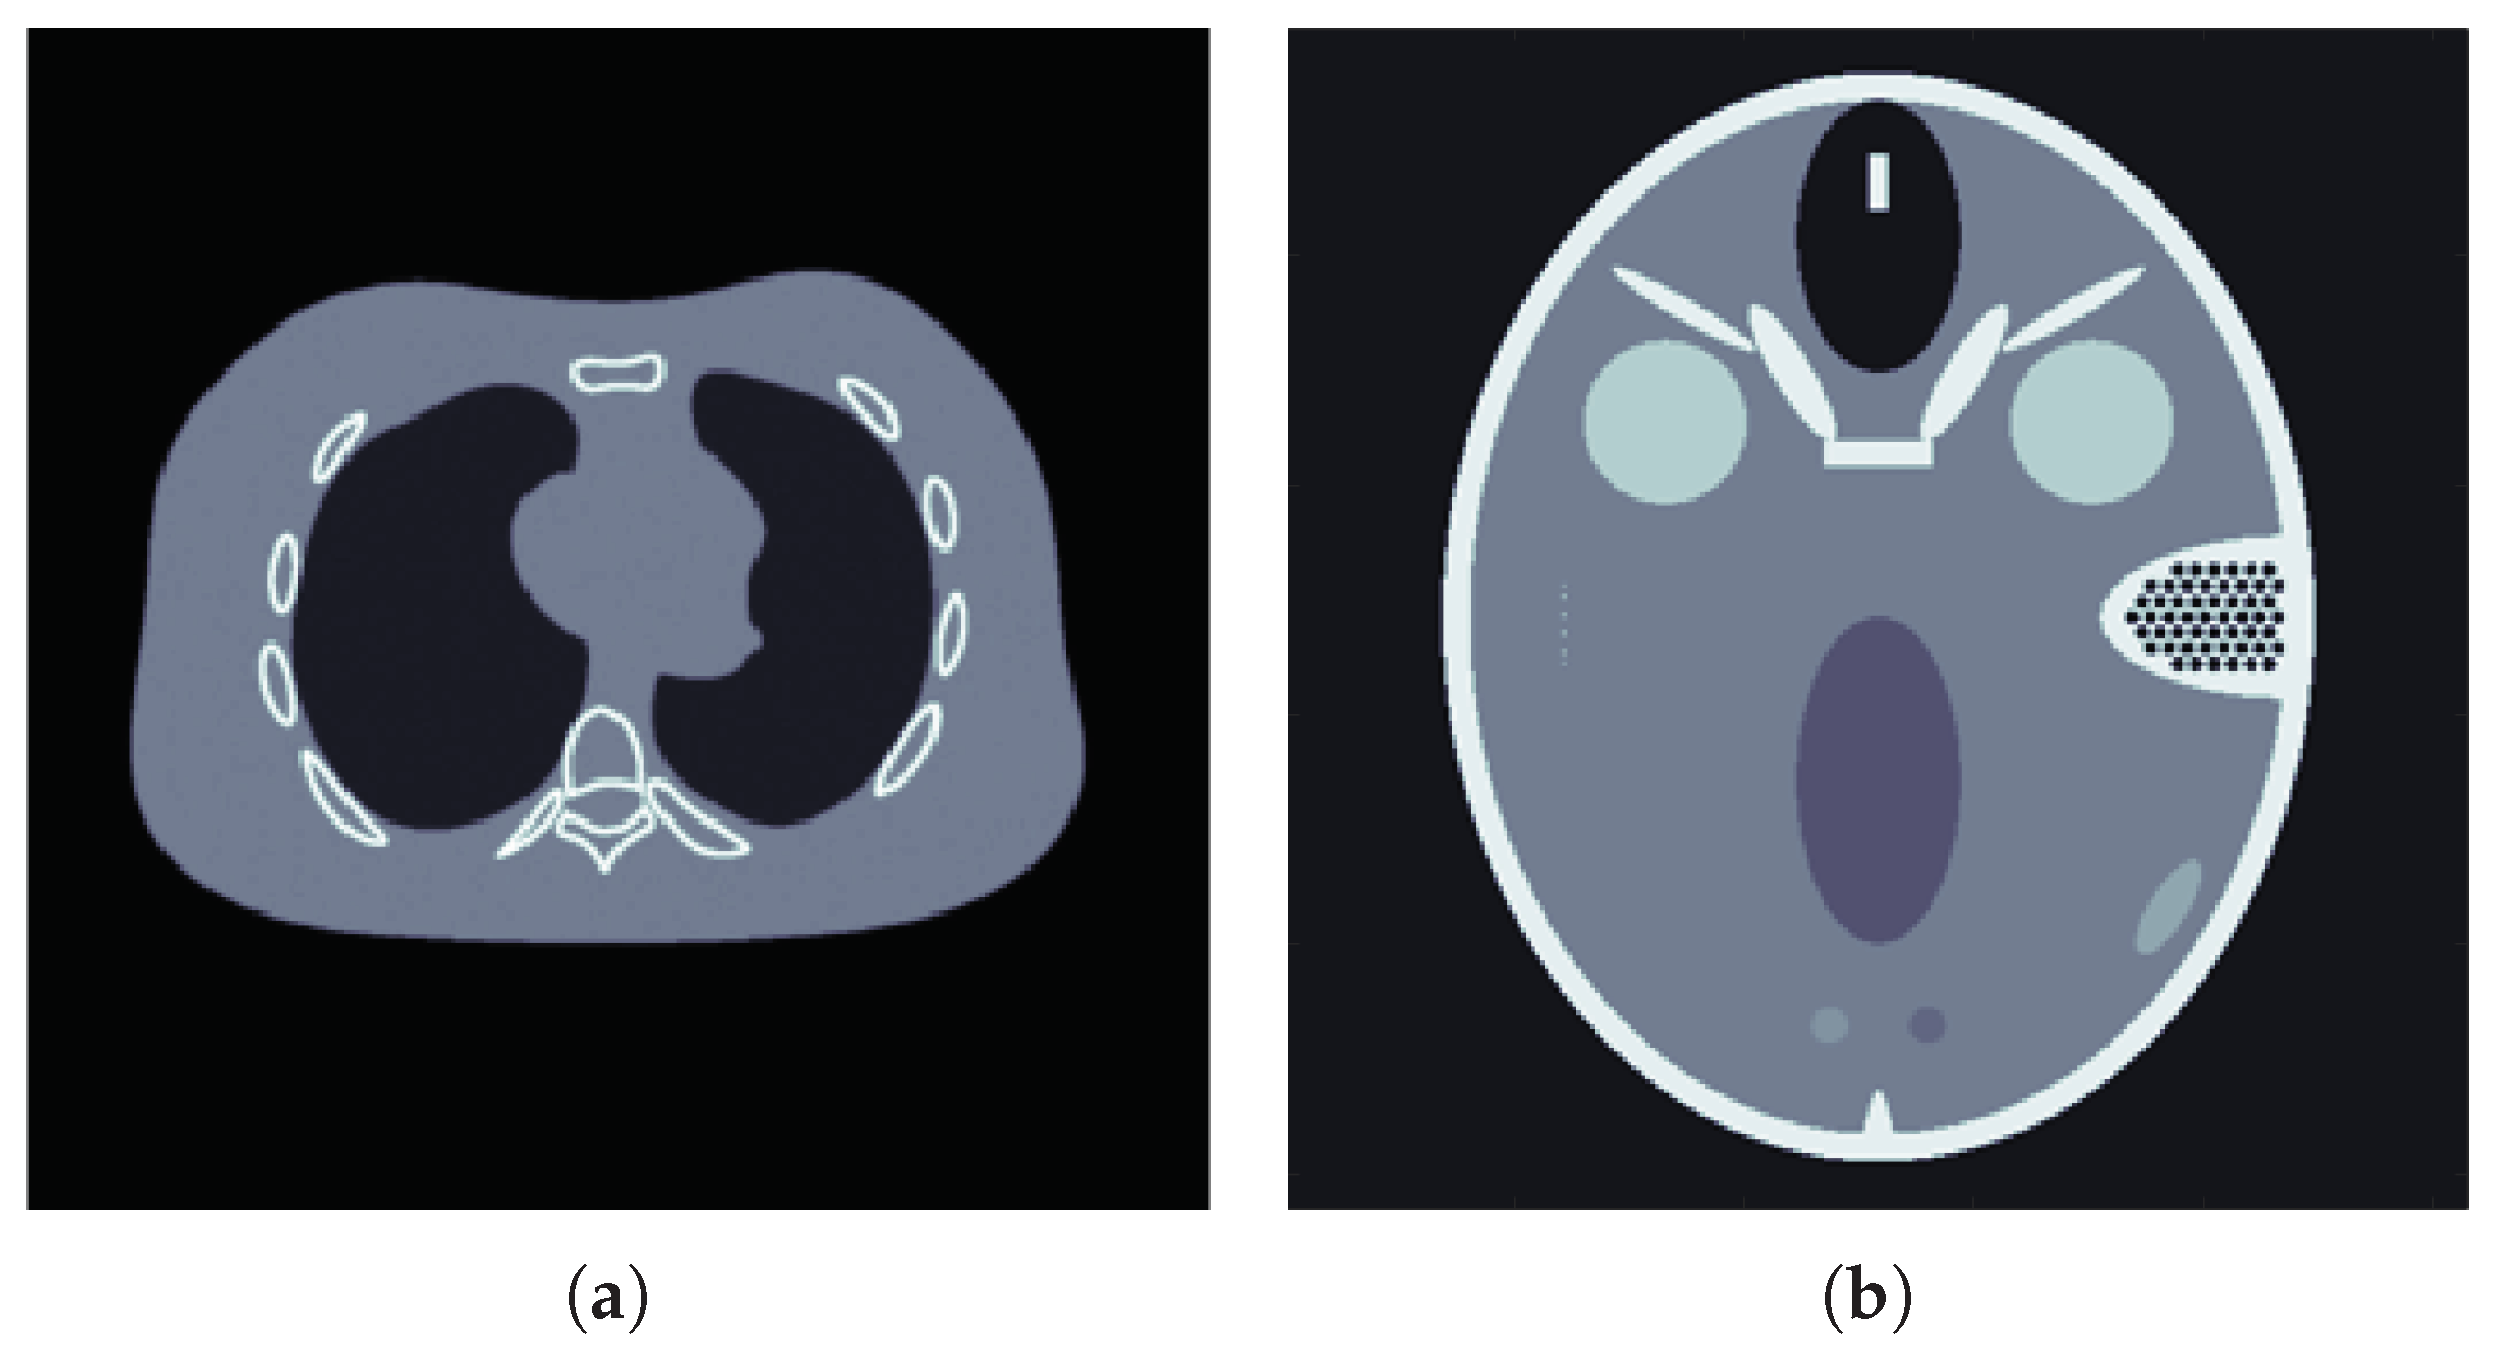

4. Numerical Experiments

4.2. Results for Limited View Data

4.3. Results for Sparse View Data